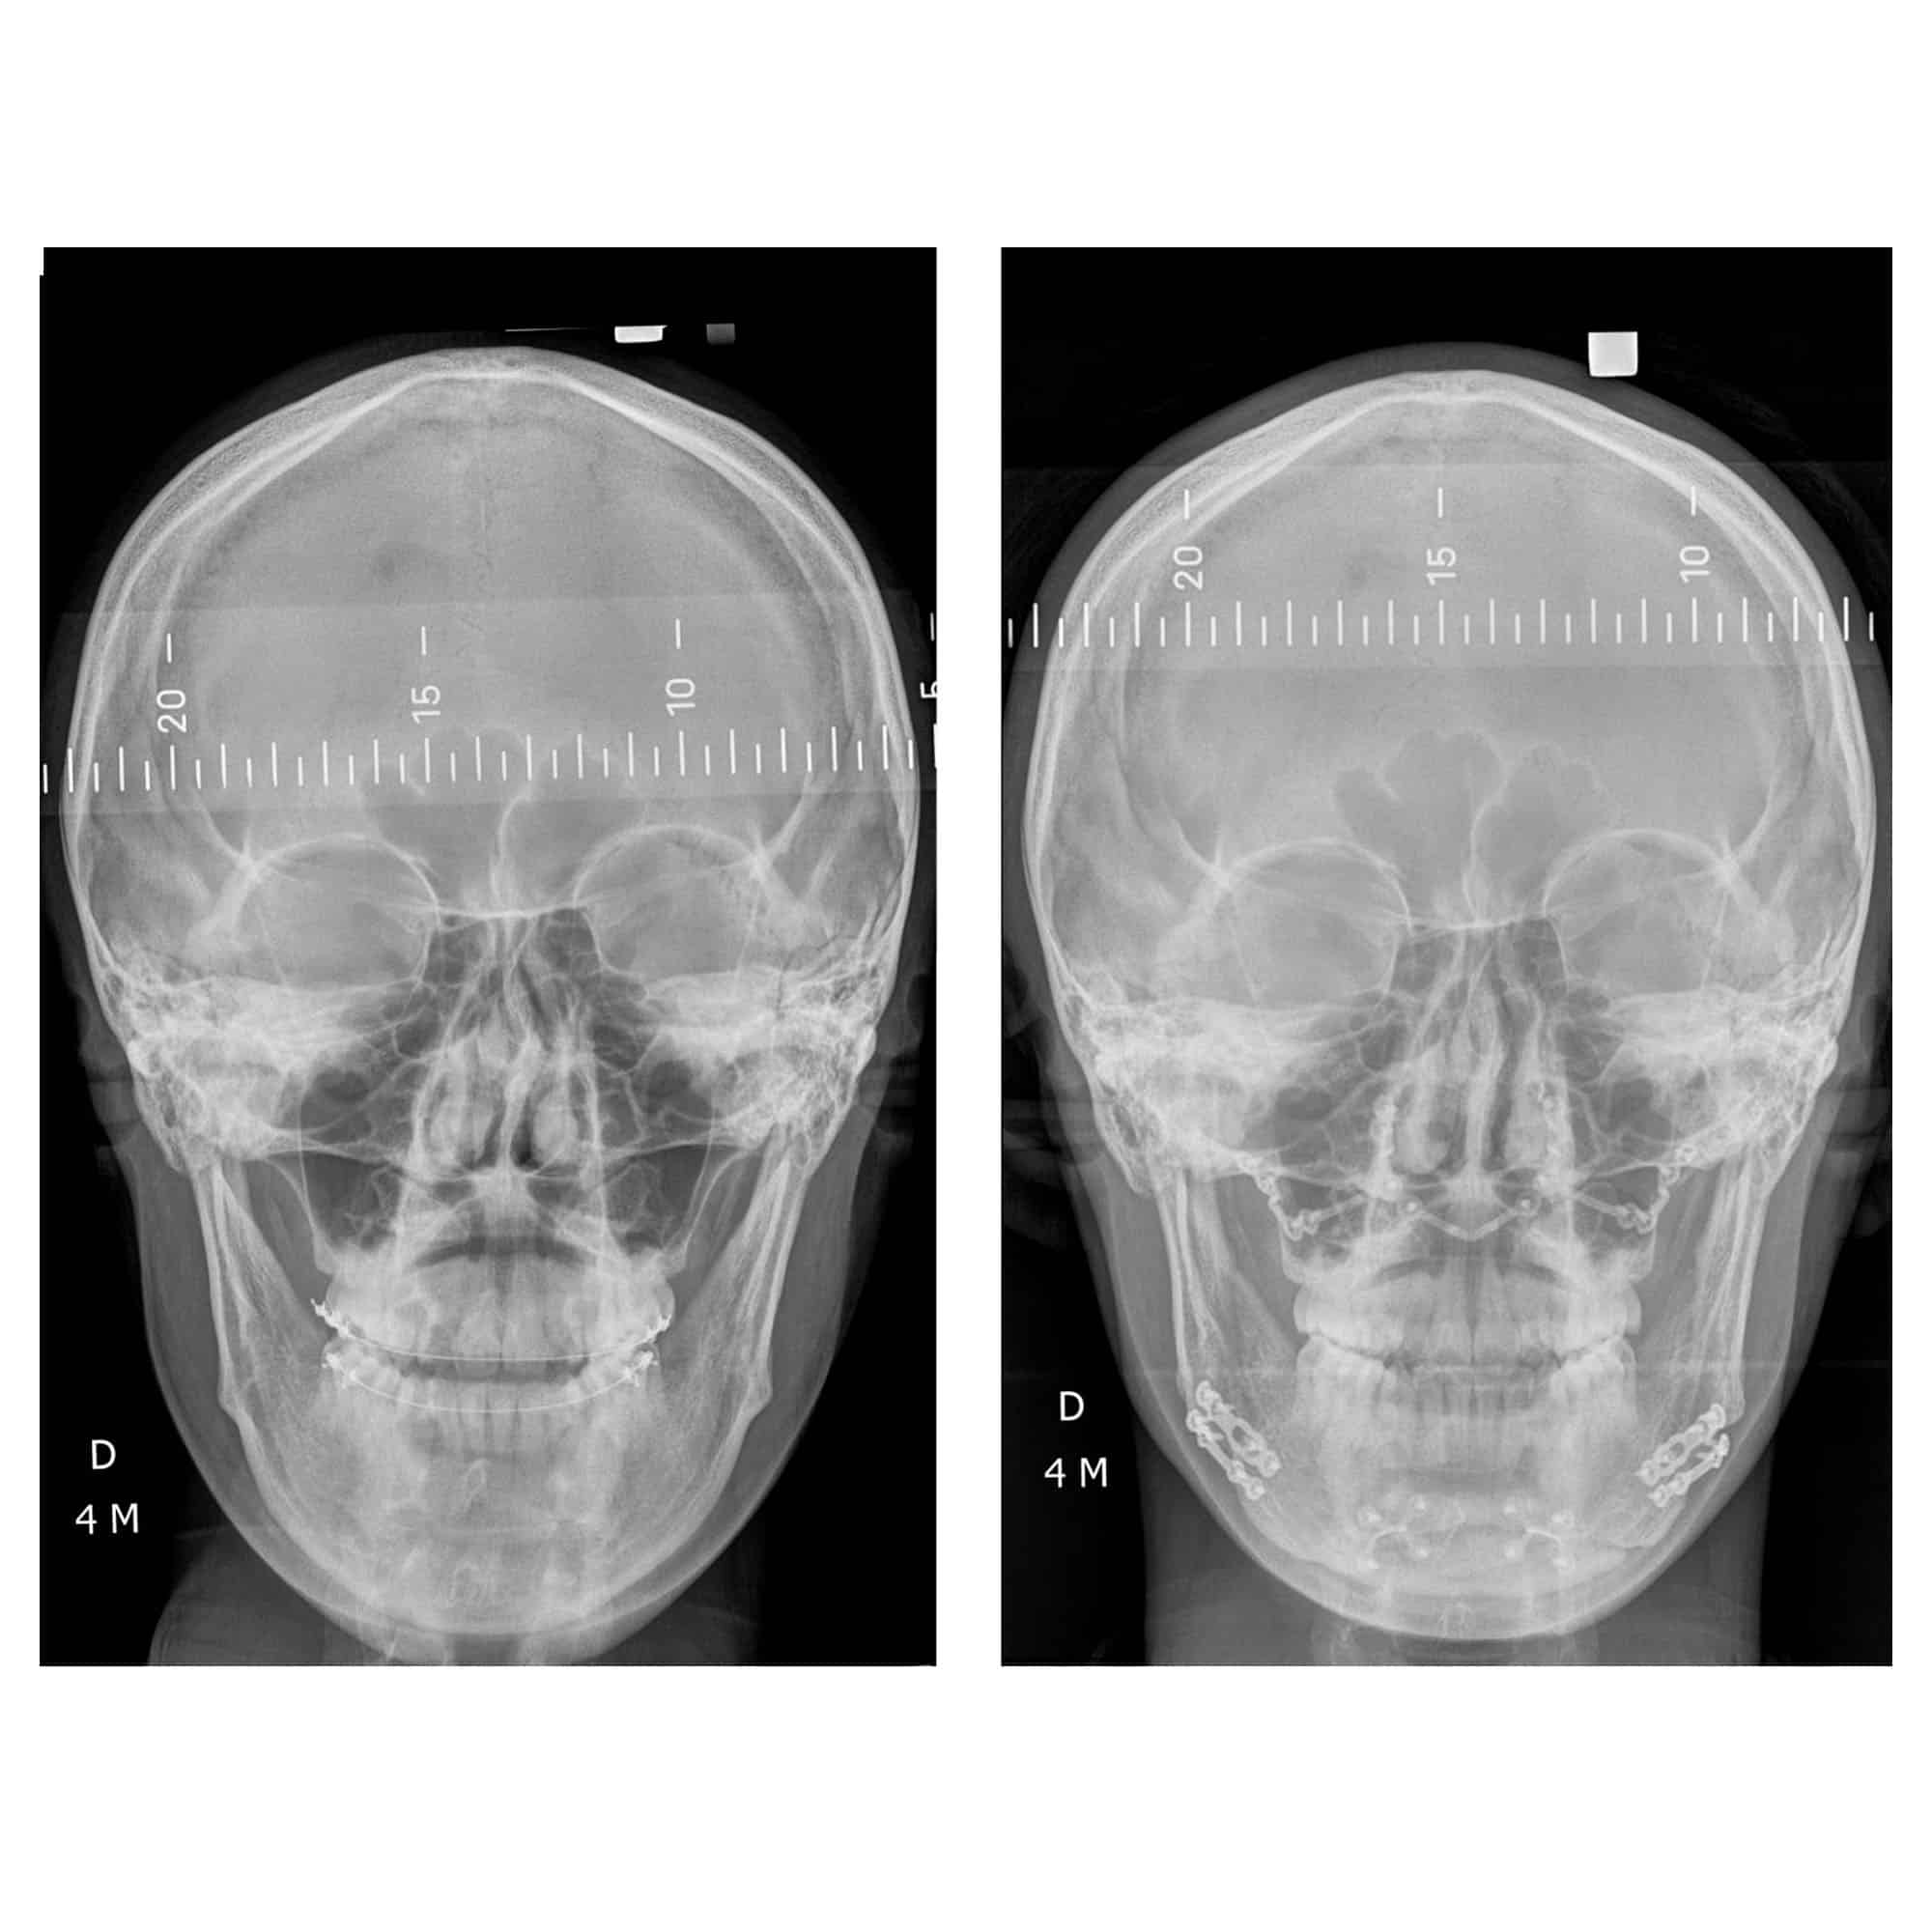

Génioplastie Paris : un exemple de génioplastie chez une patiente en traitement d’orthodontie

Voici le cas d’une patiente en Classe I squelettique mais en Classe III dentaire, du fait de la vestibulo-version des incisives mandibulaires (incisives rentrées vers l’intérieur) avec excès vertical antérieur. Cette patiente a été traitée par une rotation anti-horaire de la mandibule et une génioplastie, qui ont permis de corriger l’aspect inesthétique de départ. L’impact est aussi bien esthétique que fonctionnel, avec une amélioration de la qualité du sommeil.

Remarque sur le diagnostic et le plan de traitement : il ne fallait pas avancer le maxillaire (le haut) en raison des retentissements esthétiques néfastes potentiels mais bien faire un geste sur la mandibule (le bas). Dans tous les cas, mais encore plus ici, l’expérience du chirurgien orthognatique est cruciale afin de bien déterminer le plan de traitement adapté.

Remarque sur le traitement orthodontique associé : une fois l’intervention chirurgicale terminée, l’orthodontiste a repris son traitement et “égressé” les dents mandibulaires (du bas) pour fermer la béance postérieure générée par le mouvement chirurgical.